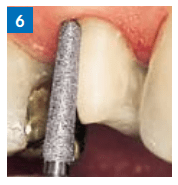

- Preparação vestibular com ponta guía 856P.314.021 para um sulco mais profundo.

Quando a profundidade é suficiente para a restauração desejada, se termina a superfície vestibular com a 8856P.314.021.